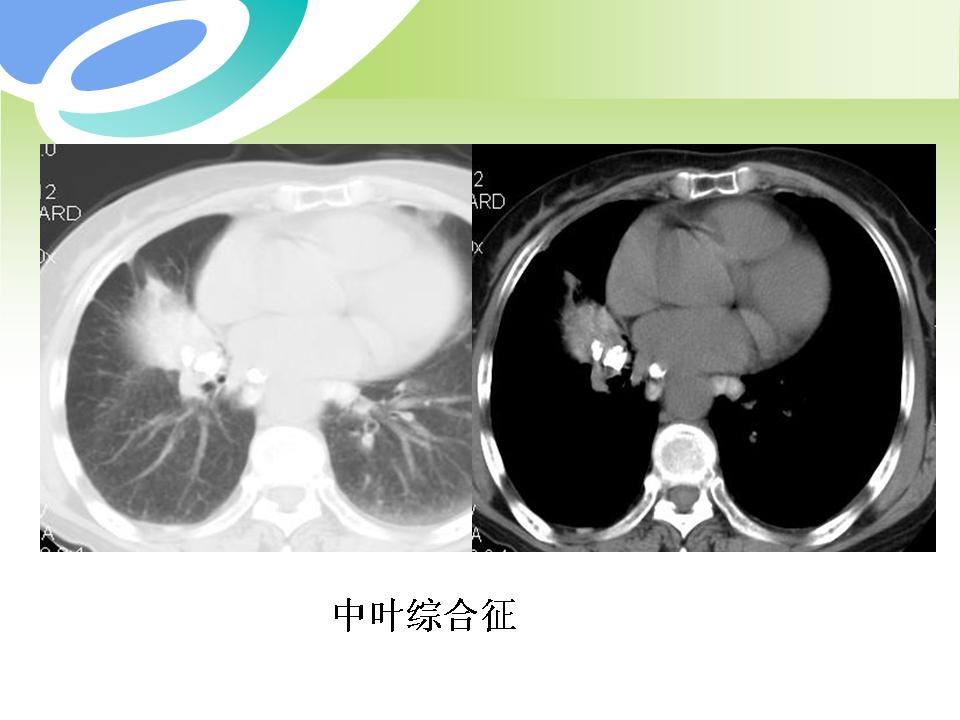

肺部病变的CT基本征象